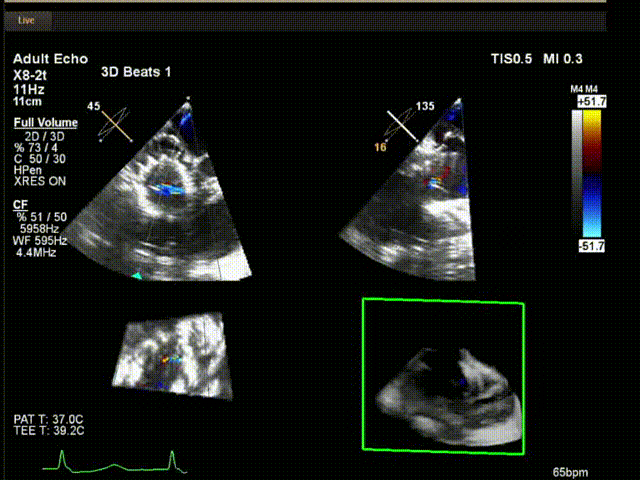

術中超聲

陸方林教授通過遠程線上帶教的方式,與林逸賢教授團隊共同完成了此次LuX-Valve Plus人工瓣膜的首例植入。術后食道超聲提示三尖瓣反流完全消失,無瓣周漏,且LuX-Valve Plus人工瓣膜的兩個夾持鍵成功抓取瓣葉,錨定牢固,人工瓣膜穩(wěn)定性良好。

林逸賢教授表示:雖然此次手術難度大,患者高齡,解剖結構復雜,但LuX-Valve Plus表現(xiàn)出非常顯著的優(yōu)勢,(1) 操作簡便,器械操作時間短(僅不足30min),器械使用流暢度和容錯率高;(2) LuX-Valve Plus輸送系統(tǒng)調(diào)彎性能好,術中可進行五維調(diào)整,保證了人工瓣膜良好的同軸性;(3) 術中對超聲影像的依賴程度低,使用經(jīng)胃底短軸切面,配合右室流入/流出道及X-Plane切面即可相當容易地獲取相關影像,以快速推進手術進程。